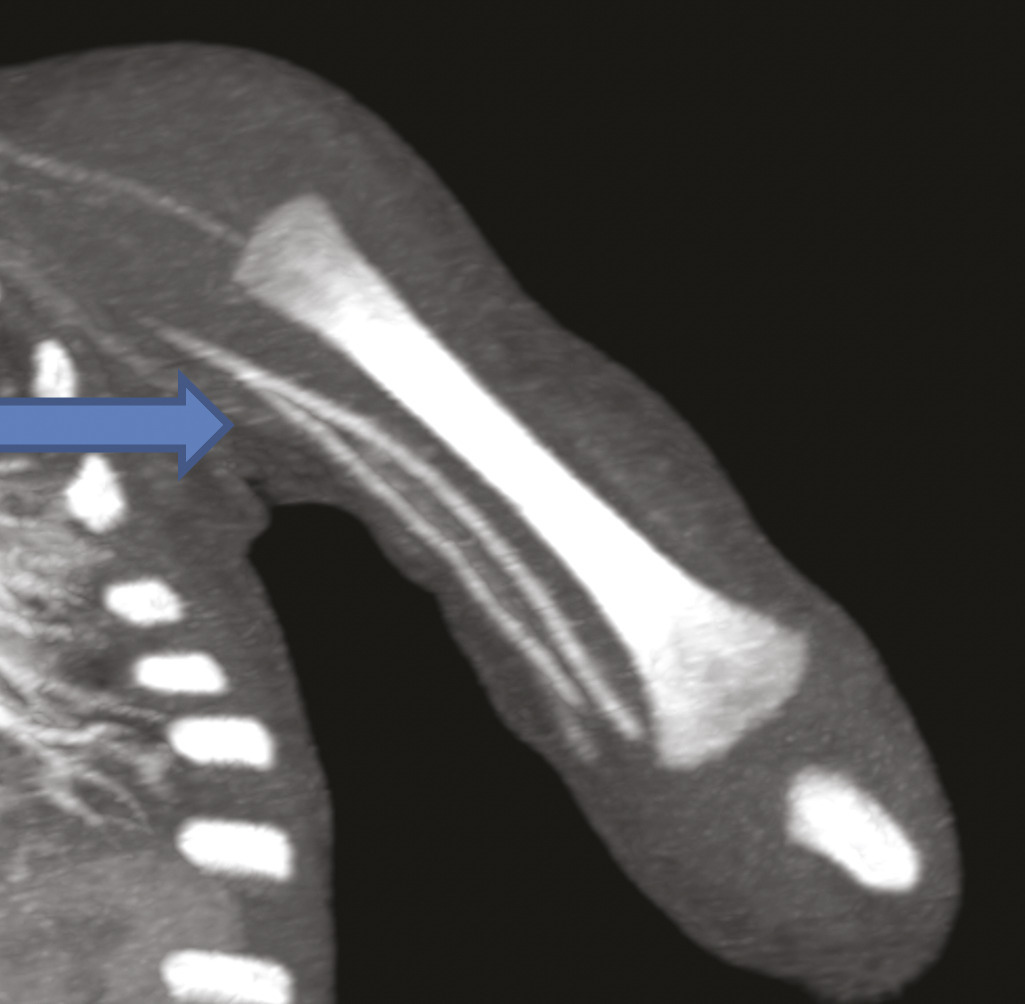

Ce nourrisson de 11 mois était hospitalisé pour l’exploration d’une masse à l’extrémité inférieure de l’avant-bras. À l’échographie, on notait une formation tissulaire hypervasculaire au Doppler couleur, motivant un complément d’investigations. L’imagerie par résonance magnétique étant techniquement difficile à réaliser, un angioscanner a été demandé, qui montrait (fig. 1 et 2 ) une tumeur vasculaire à développement essentiellement sous-cutané respectant les structures musculaires et osseuses. Il mettait en évidence une variante anatomique : une origine haute de l’artère radiale sans cross-over avec l’artère cubitale.